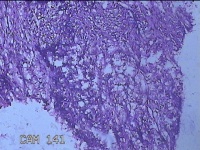

左大腿内侧包块

性别

男

年龄

21岁

临床诊断

脂肪瘤

一般病史

左大腿内侧起包块一月余。

标本名称

大体所见

灰白暗红色包块2.5x2x0.8cm一个,表面糜烂,切开包块呈实性,切面灰白暗红色,质软。